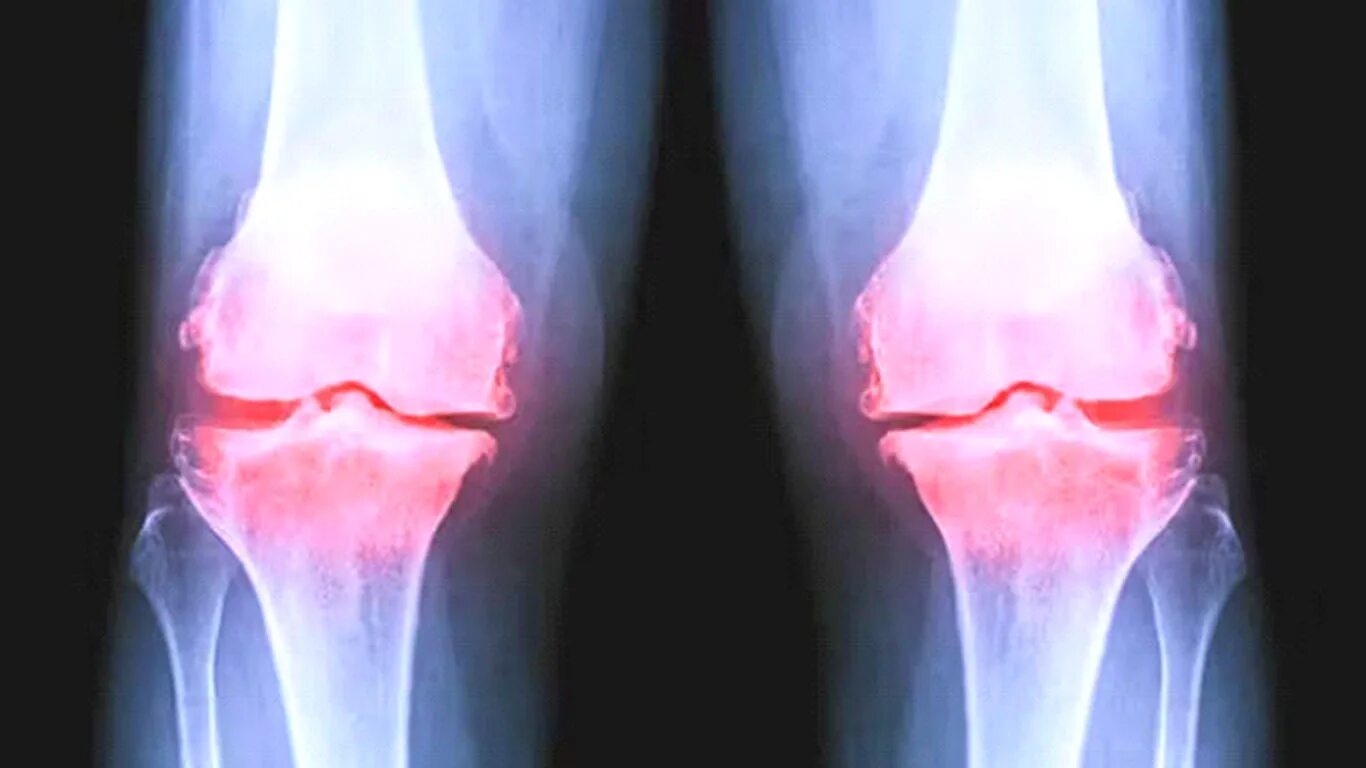

Что такое деформирующий артроз коленного сустава